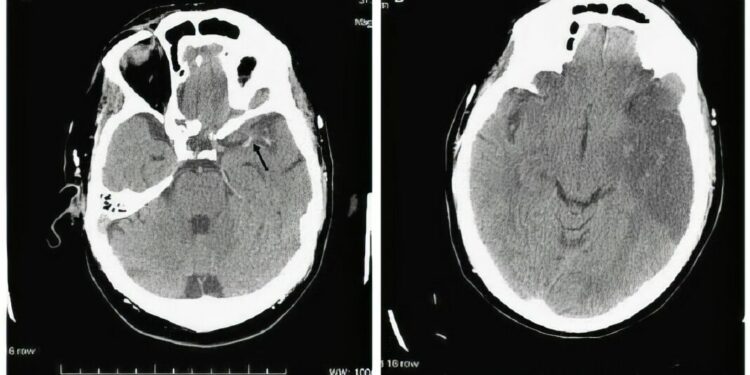

La primera aplicación de este tratamiento se realizó el pasado mes de febrero a una paciente sin antecedentes médicos relevantes, que presentó síntomas como pérdida de fuerza en el lado derecho, dificultad en el habla y asimetría facial. Tras ser derivada de urgencia al hospital majorero, se confirmó el diagnóstico de ictus isquémico agudo y se procedió a la administración del nuevo trombolítico.

El equipo de especialistas en Neurología del centro actuó dentro de las primeras tres horas desde la aparición de los síntomas, respetando la ventana terapéutica recomendada de cuatro horas y media. Esta rápida intervención fue clave para favorecer una mejor evolución clínica de la paciente.